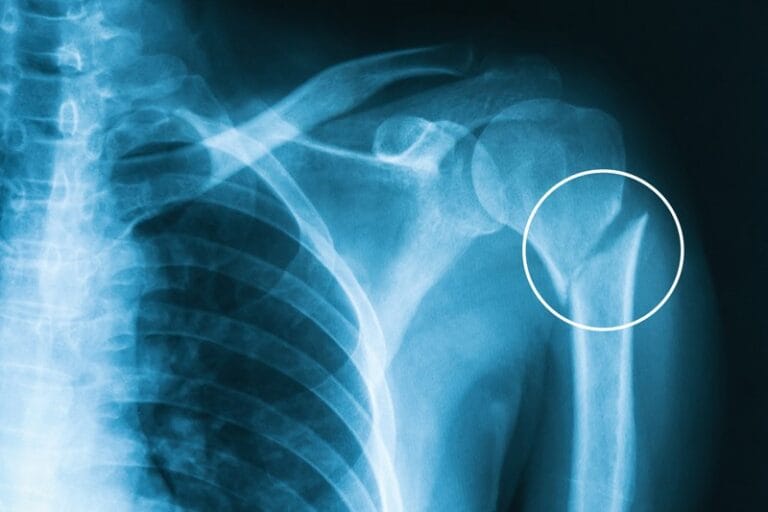

Diagnostic Tools:

- Physical Examination: Tenderness along the bone, especially when pressure is applied.

- Imaging: X-rays may not reveal a stress fracture initially. An MRI or bone scan is more effective in identifying early-stage stress fractures